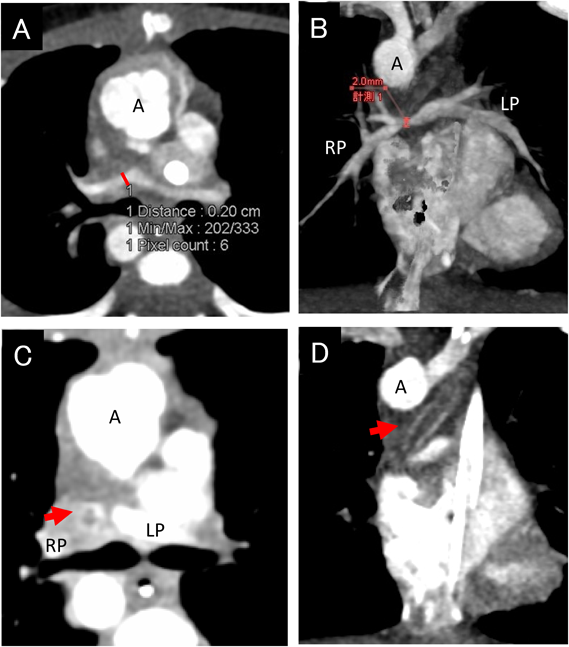

CT画像からは広範囲な気管低形成が認められた.当初転院予定だった他院小児外科と協議の結果,肺動脈スリングと大動脈弓による圧排が増悪因子となっており(Fig. 2A, B),気管形成のみでは今回の呼吸循環不全からの回復は困難であると考えられ,日齢43に肺動脈スリング解除術および上行大動脈吊り上げ術を施行し,引き続いて,日齢46に気管形成術を施行した.術後の気管支ファイバーにて気道狭窄はなく,人工呼吸器の1回換気量は改善したがECMOを離脱できなかった.術後4日目に開胸洗浄を行った際に主肺動脈に血栓を認め,血栓除去術を施行した.その際に末梢肺動脈から血液の逆流がなかったため,さらに遠位に血栓が及んでいる可能性が示唆された.術後5日目に肺動脈の評価目的に再度造影CT検査を施行した(Fig. 2C).

Fig. 2 CT angiograms of Case 2

(A) The trachea is severely stenotic (Tr). (B) The left PA surrounds and compresses the trachea. The right PA is completely narrowed and hypoplastic. SVC: superior vena cava, Ao: aorta, MPA: main pulmonary artery, LPA: left pulmonary artery, RPA: right pulmonary artery, Tr: trachea, VL: venous line of ECMO, AL: arterial line of ECMO. (C) View of the CT examination under ECMO support. (D) A follow-up CT angiogram of case 2. The left and right pulmonary arteries are not clearly enhanced (red arrow). Ao: aorta, SVC: superior vena cava.

ECMOの条件および移動手段は前回と同様で,CT検査も同様に心電図同期管電流変調を併用したECG同期法を用い,ピッチ0.46(撮影中心拍数114~115 bpm),管電圧70 kV,管電流130 mAs/rotationで呼吸停止下に撮影した.造影剤も前回と同様に2倍希釈したもの15 mL(7.5 mL/kg,原液で2.5 mL/kg)を0.5 mL/秒で下肢末梢静脈から注入し,注入開始25秒後に撮影を開始した.CT所見では,左右肺動脈幹の造影は乏しいが両側の末梢肺動脈は造影され,末梢肺動脈は開存していると判断し,シャント手術による肺血流の確保を考慮した(Fig. 2D).気管形成術後であり,人工物使用を避けるために,同日に左original Blalock–Taussig shunt手術を実施した.また術後7日にさらに右original Blalock–Taussig shunt手術を追加した.その後患児の状態は改善し,術後17日目(日齢63)にECMOから離脱した.術後経過も順調であり,現在Glenn手術を待機している.

術後28日目頃より間質性肺炎を発症し増悪した.術後43日のCT検査では,両側肺野にスリガラス状陰影を認め(Fig. 3A),ステロイドパルス療法を行ったが改善なく,NPPVを再度導入したが呼吸不全が進行した.術後45日に再挿管し人工呼吸器管理となるがさらに増悪し,術後46日にECMOを導入となった.術後48日には左肺に肺出血をきたし保存的に加療し止血を待った.術後62日にフォローアップ目的でECMO下の胸部単純CT検査を施行した.検査室への移動には医師2名,看護師2名,臨床工学技士が2名同行した.CT検査はFlash Spiral法を用い,ピッチ1.0として呼吸停止下に撮影した.スリガラス陰影の改善傾向(Fig. 3B)および気管内からの新鮮血の消失を確認し,術後64日にECMOを離脱した.以後も理学療法を継続し,肺野の異常陰影はやや残存するも,術後69日に無気肺は大幅に改善した(Fig. 3C).

Pediatric Cardiology and Cardiac Surgery 33(1): 69-75 (2017)

Fig. 3 CT of case 3

(A) Day 43 postoperatively: ground-glass opacities are present in both lung fields. (B) Day 64 postoperatively: ground-glass opacities are improving. Left lung is collapsed due to atelectasis. (C) Day 69 postoperatively: atelectasis almost disappeared. Ground-glass opacities are not detected.